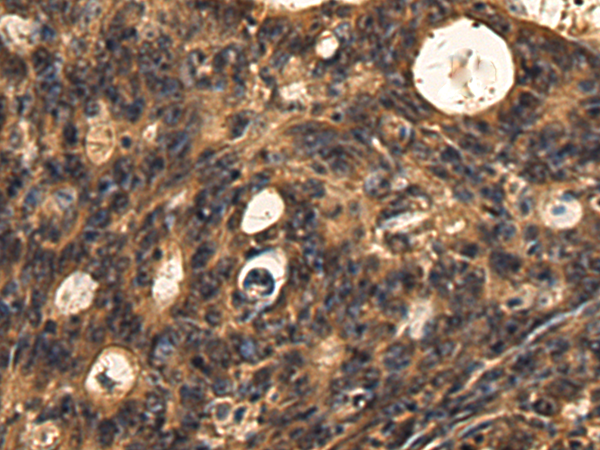

分类: 科研抗体货号: P10442别名: IF; GIF; INF; IFMH; TCN3应用: IHC反应种属: Human, Mouse, Rat